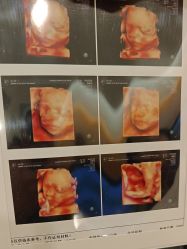

• -杭州贝瑞斯美华妇儿医院·早孕·产检·儿科

相册

橙枝锦 上传于 25-07-27 | 报错